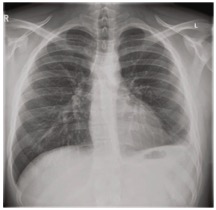

由于患者拒绝手术,因此将第二个ICD插入基底部,胸腔内再次给予10mg阿替普酶,来尝试清除胸膜腔并破坏胸膜粘连。四天后进行的胸部CT显示有显著改善,残余液体最少,肺萎陷几乎完全再扩张(图1d)。两个ICD都被移除,患者第二天出院。整个住院期间血红蛋白保持稳定,无需输血。在两周后的随访中,患者完全康复,CXR显示左肋膈角的钝化程度最小(图2)。

图2. 出院后2周的胸片,肺野清晰,左肋膈角轻度变钝